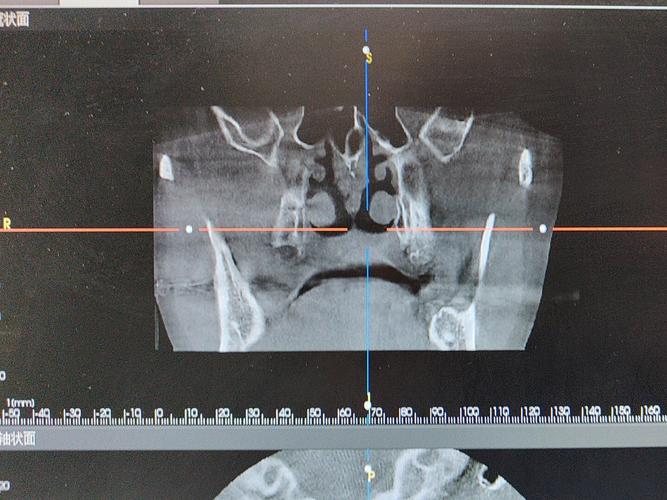

ICX系统植牙需遵循严格的临床流程,确保治疗安全与效果,术前,医生需通过CBCT、口腔全景片等影像学检查评估患者牙槽骨的密度、高度、宽度,结合全身健康状况(如是否有糖尿病、骨质疏松等)制定个性化方案;术中在局部麻醉下微创手术植入种植体,切口小(通常3-5mm),出血少,手术时间约30分钟-1小时(单颗牙);术后需服用抗生素预防感染,避免患侧咀嚼,1周后拆线,进入3-6个月的骨结合期。